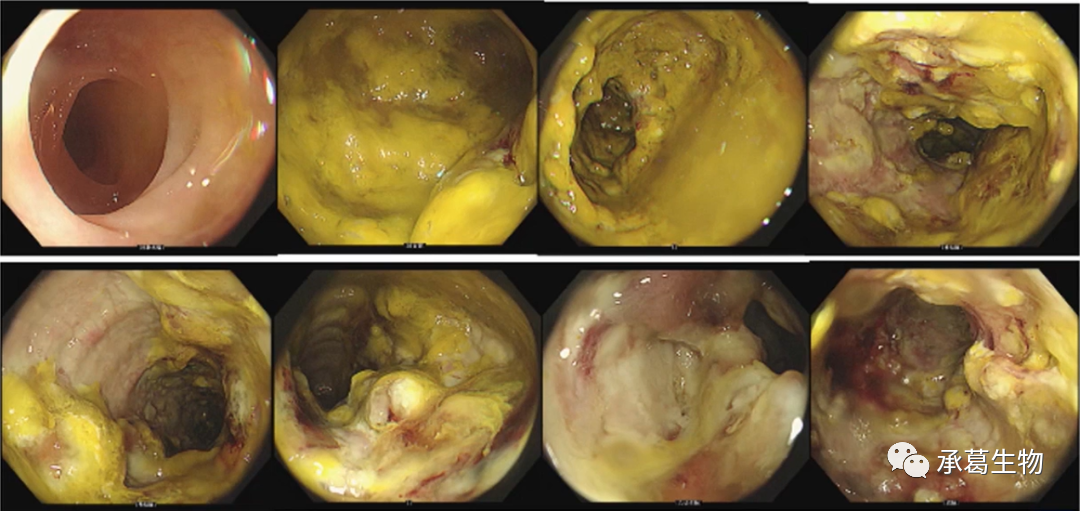

2021年2月患者再次腹瀉,約4-5次/日,伴粘液、鮮血。中成藥治療無效,腸鏡提示結(jié)直腸充血水腫、散在潰瘍,病理提示炎性細(xì)胞浸潤,患者拒絕住院進(jìn)一步檢查??紤]潰瘍性結(jié)腸炎(慢性復(fù)發(fā)型,全結(jié)腸型,活動(dòng)期,中度),予美沙拉嗪及調(diào)節(jié)腸道菌群治療。4個(gè)月后腹瀉較前明顯改善,腸鏡提示升結(jié)腸散在片狀潰瘍、并行內(nèi)鏡下息肉切除術(shù),繼續(xù)美沙拉嗪治療。

(2021年2月腸鏡)

2022年5月因勞累再次腹瀉加重至10余次/日,大便粘液、鮮血,伴全身乏力、左下腹痛,里急后重,住院治療。血常規(guī)示HGB 122G/L(輕度貧血),ALB 32.2g/l(低蛋白血癥),糞常規(guī)示W(wǎng)BC+,RBC++,隱血陽性,CRP及血沉均輕度升高。腸鏡提示全結(jié)腸彌漫水腫伴不規(guī)則潰瘍形成,結(jié)腸袋消失,病理示粘膜慢性炎癥,可見中性粒細(xì)胞。診斷為潰瘍性結(jié)腸炎(全結(jié)腸型、急性活動(dòng)期,重度)。予美沙拉嗪、激素治療,腹瀉次數(shù)減至4-5次/日,粘液膿血減少,出現(xiàn)血糖控制不佳,激素減量后腹瀉5-6次/日。予維得利珠單抗治療3次,排便次數(shù)2-3次/日,無明顯粘液膿血。

(2022年5月腸鏡)